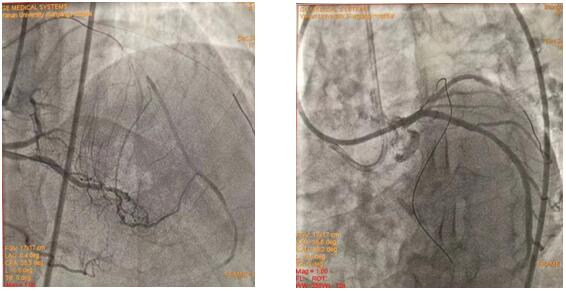

(插圖說明:圖1為雙側造影圖、圖2為導絲正向通過圖、圖3為求那邊、圖3為球囊通過圖、圖4為導絲逆向通過圖)

在吳棟梁院長的協調安排下,從12月24日清晨7:30到12月25日清晨7:50安全完成62例介入手術。其中,心血管內科二病區介入團隊在左梅主任的帶領下,清晨七點半開始,C3830電極對于左束支區域起搏、永久起搏器的成功置入,逆向技術開通LAD近段無殘端閉塞病變的順利完成,創造著一個個生命的奇跡,為心血管病患者帶來一個不平凡的平安夜。